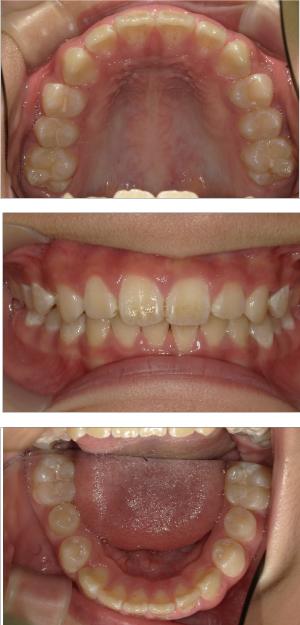

バイオブロック矯正(顎顔面口腔育成治療)

矯正治療は大人になって始めるよりも子どもの頃から始めた方が確実に良い結果をもたらします。成長が盛んな子供の時期に、顎や顔の成長を利用しながら治療ができる大きなメリットがあるからです。当院では、非抜歯矯正を推奨しておりバイオブロック矯正を取り入れています。

バイオブロック矯正の考え方は歯並びが悪くなる原因にアプローチする治療法になります。

舌の位置や口呼吸から乱れてしまった下顎の後退を正し、顎顔面が本来あるべき位置へと誘導させていく治療です。

- 歯並びの改善

- 歯を動かすのではなく顎の成長を促す

- 非抜歯矯正ができる

- 側方拡大だけでなく前方成長も促す

- お顔の成長が正しく美しく導くことができる